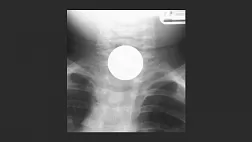

Иллюстрация №2: Инородное тело (монета) пищевода

Т.к. большинство истинных инородных тел рентгенконтрастны, диагностическим методом выбора является рентгенография (шеи, грудной клетки и живота) в нескольких проекциях (чаще фронтальной и боковой).